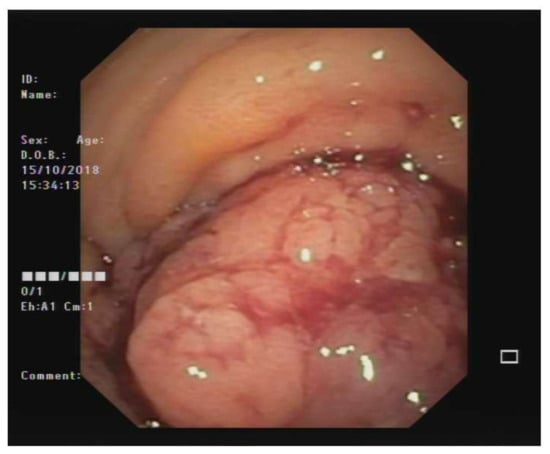

Sequence analysis of DNA extracted from the patient’s blood excluded the presence of germline variants in cancer predisposition genes, such as in Li-Fraumeni syndrome gene TP53 (OMIM #151623), adenomas multiple colorectal gene MUTYH (OMIM #608456), adenomatous polyposis gene APC (OMIM #175100), and mismatch repair genes (MMR) MSH2, MSH6, MLH1, MLH3, and PMS2). Furthermore, high-coverage sequencing on the DNA extracted from the patient’s tumor sample did not reveal any detectable somatic variant in the therapeutic target genes KRAS, NRAS, and BRAF but showed the presence of a missense change in the TP53 gene (NM_000546.5), c.733G>A (p.Gly245Ser), with an allele burden of 8% (according to NGS performed at high depth >500X) (Figure 4). This variant has been previously reported to segregate in multiple families with Li-Fraumeni syndrome (PMID: 1565143, 24122735, 17311302) and was found to be a somatic alteration in several types of cancer (COSM6932) [8]. Experimental studies have shown that this variant disrupts the ability of TP53 to bind to DNA and significantly decreases its transcriptional transactivation activity (PMID: 12826609, 20128691). This missense substitution can be classified as a pathogenic variant (class 5) according to the ACMG guidelines, on the basis of PS3, PM1, PM2, PP3, and PP5 criteria [9].

Figure 4. Integrative Genome Viewer (IGV) screen with the variant identified in blood (upper) and tumor DNA (down). Note the allele burden greater than 8% supporting the mosaic alteration of TP53 variant. Scale bar: 100 µm.